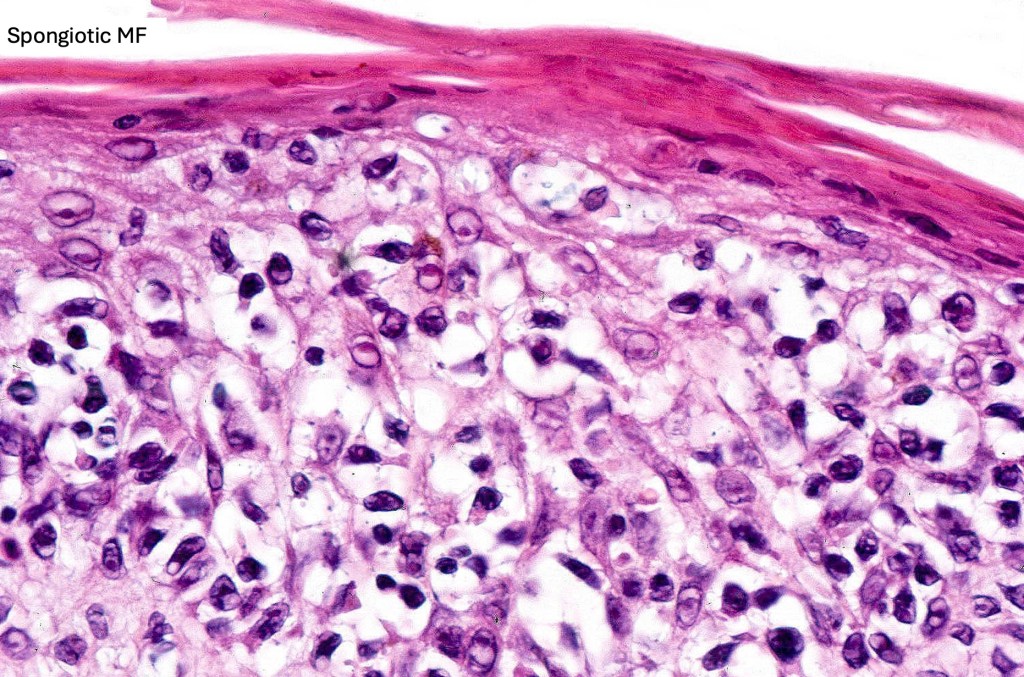

Histological features

The histological hallmark of mycosis fungoides is the presence of large atypical lymphocytes with a convoluted/cerebriform nuclear border (Sézary cells). These may be found at the epidermal-dermal jnuction and as collections within the epidermis (Pautrier microabscess). These are most easily found in plaque stage disease. The epidermal component can be subtle in patch stage disease and is often lost in tumor stage dsease. The classification into patch, plaque & tumor stage disease is less helpful histologically as the features merge from one to the other. It is all a matter of degree.

Patch stage disease

•Changes can be subtle & dependent on clinicopathological correlation; in many patients sequential biopsies over many months may be necessary to establish the diagnosis.

•Mild hyperkeratosis & focal parakeratosis, acanthosis, epidermal atrophy or of normal thickness

•Superficial dermal lymphocytic infiltrate containing variable numbers of Sézary cells with atypical, irregular, hyperchromatic nuclei surrounded by a halo; these can be very few in number and dependant on viewing multiple levels

•Palisading of atypical lymphocytes along the epidermal-dermal border

•Pautrier microabscesses may be present but are often absent in patch stage disease

•Variable interface change with keratinocyte necrosis & pigmentary incontinence

•Eosinophils & plasma cells sometimes present

•Coarse collagen bundles in the papillary dermis can be a feature but this is not as marked as seen in plaque disease

.Although in typical mycosis fungoides fungoides, spongiosis is absent, exceptionally it can be a feature